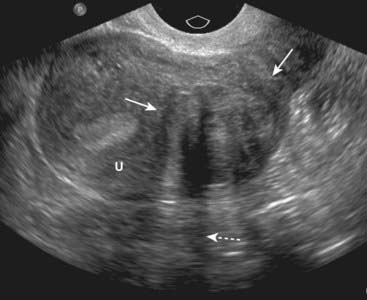

image Recognizing uterine leiomyomas on US

Uterine leiomyomas are heterogeneously hypoechoic, solid masses, meaning they may display some areas that contain many echoes and others that demonstrate few echoes. They frequently absorb enough sound to produce acoustical shadowing. Where they are necrotic, they may be anechoic. If they contain calcium, the calcium will produce acoustical shadowing (Fig. 19-15).

image

Figure 19-15 Leiomyoma of the uterus, sagittal view.

There is a heterogeneously hypoechoic mass (solid white arrows) in the uterus (U). Uterine leiomyomas may display some areas that contain many echoes and others that demonstrate few echoes. They frequently absorb enough sound to produce acoustical shadowing (dotted white arrow). Where they are necrotic, they may be cystic. If they contain calcium, the calcium will produce acoustical shadowing.